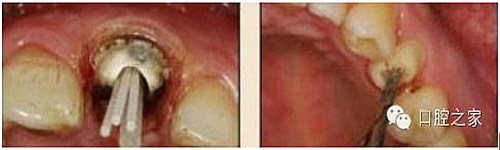

8.根管內(nèi)酸蝕劑的去除

使用全酸蝕粘結(jié)系統(tǒng)粘接纖維樁時(shí),需要應(yīng)用磷酸凝膠對(duì)根管進(jìn)行酸蝕處理,然后再?gòu)氐讻_洗干凈。根管內(nèi)酸蝕劑的殘留是臨床上經(jīng)常發(fā)生且容易被忽視的問(wèn)題,也是影響纖維樁粘接的重要因素之一。單獨(dú)使用三用槍即使反復(fù)沖洗也很難將根管內(nèi)的酸蝕劑清除干凈,尤其是后牙根管。臨床建議應(yīng)用注射器、三用槍和柱狀毛刷,三者聯(lián)合使用反復(fù)沖洗,以免酸蝕劑殘留于根管內(nèi)(圖 19-1至圖 19-4)。有條件者也可使用超聲波蕩洗根管。

圖19-1:冠部及根管全酸蝕。圖19-2:三用槍沖洗。圖19-3:注射器沖洗。 圖19-4:根管毛刷清洗。